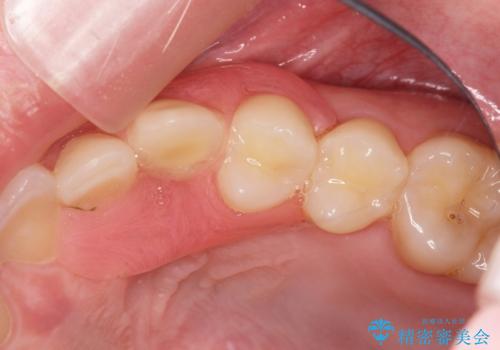

型取りと装着の2回で治療を終了することができました。

- ブリッジやインプラントと比較して、色が合いづらい、見た目の違和感があります

- ブリッジやインプラントと比較して、話しにくい、舌が当たる等の違和感があります